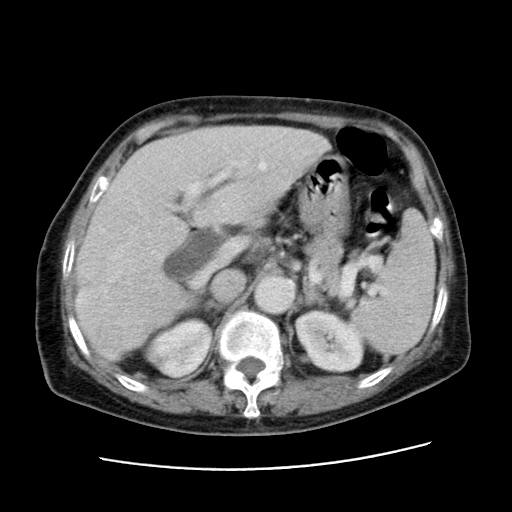

女,77.无不适

肝脏变异、异位胆囊,肝右叶肝内胆管结石并肝内胆管扩张。

肝内胆管扩张,胆囊炎,胆囊窝积液。 右侧胸腔少量积液。

肝脏变异

肝右叶肝内胆管结石并肝内胆管扩张

肝右叶肝内胆管结石并肝内胆管扩张。另:慢性胆囊炎!胆囊窝积液!